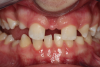

Fig 8. Photograph, 14-year-old brother.

Figure 8

Figure 5 through Figure 12 exemplify what currently may present in private dental practices with these types of patients. Four brothers aged 14 years to 27 years all suffered from obstructed airways; high incidence of caries of dentin, enamel, and cementum; moderate periodontal disease; collapsed vertical; undiagnosed OSA; and the potential for increase in comorbidities such as diabetes, cardiovascular disease, dementia, cancer, high blood pressure, and others. Symptomology was presented throughout the young lives of the brothers in this family. The parents were unaware that the dental agenesis and premature permanent tooth extraction could have led their sons into severe health issues as they matured.

Swift intervention took place with caries control, periodontal care, orthodontic evaluation for arch form development to aid in the development of facial bones and creating an improved upper airway with nasal patency. These interventions were followed up with definitive implant therapies and rapidly advancing restorative technology and materials. Thus, not only were these young men's smiles restored, they also were provided with the opportunity to regain their dignity when they become confident with their new smiles.